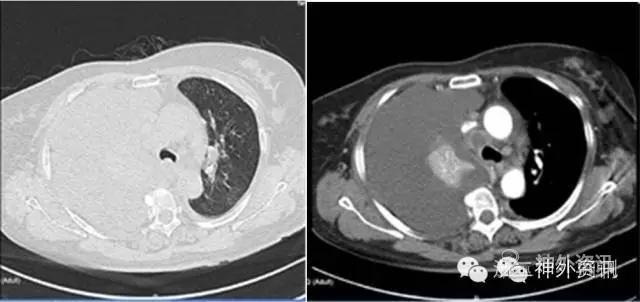

进一步查肿瘤标记物,除提示CA125124.2U/ml,较正常高3-4倍,余正常。同时行胸部增强CT检查,提示右肺下叶中央型肺癌可能,伴肺不张,右侧胸腔积液较前增加,纵隔多发淋巴结转移。左肺也见数个结节,转移不除外(图5)。全身ECT骨显像提示肋骨、椎体、下肢等部位多发骨转移(图6)。

图5. 胸部CT显示右侧肺癌伴肺不张和胸腔积液。